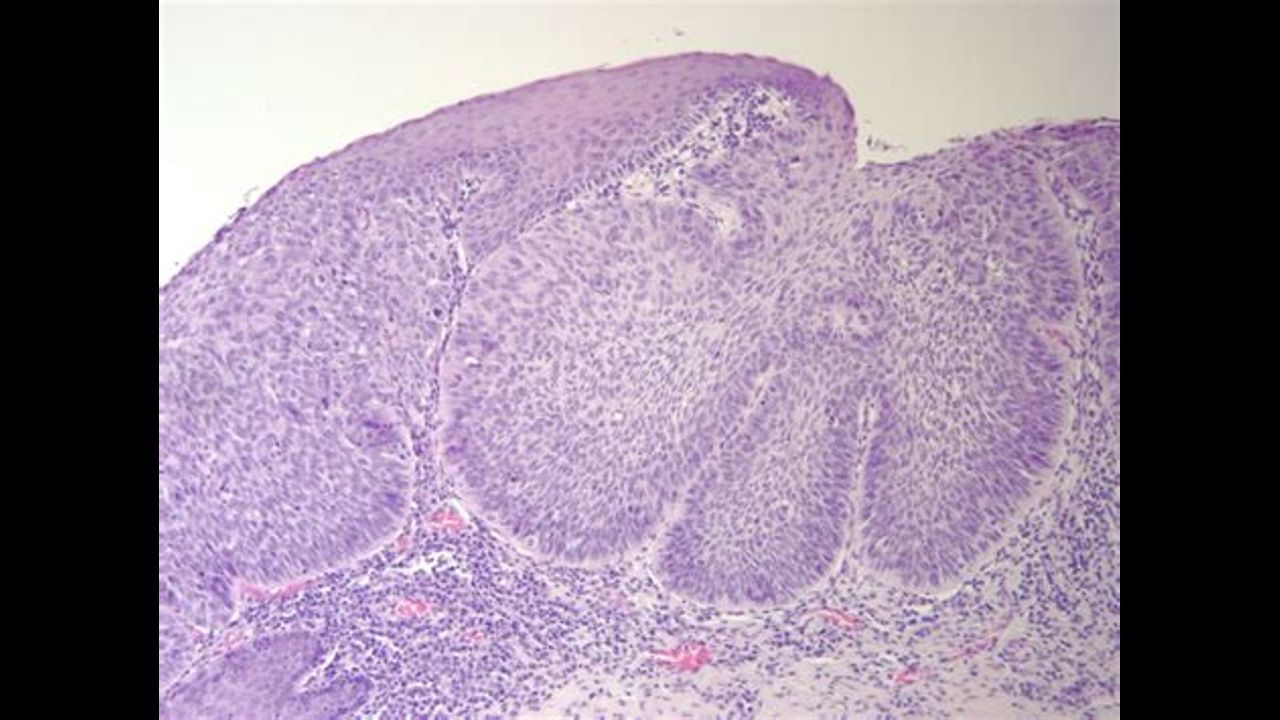

THE PATHOLOGIST PROF. ARNE BURKHARDT MD: "COVID-19 "VACCINES" CAN INDUCE SELF-DESTRUCTION"